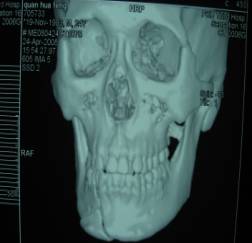

主要包括牙槽外科手术(含各种牙齿的拔除、牙槽骨修整手术、牙种植术等),口腔颌面部炎症及颞下颌关节疾病的诊断与治疗,口腔颌面部创伤(含颌面部软组织创伤及骨折)的诊断与治疗,口腔颌面部及唾液腺(腮腺、颌下腺、舌下腺)肿瘤的诊断与治疗等。